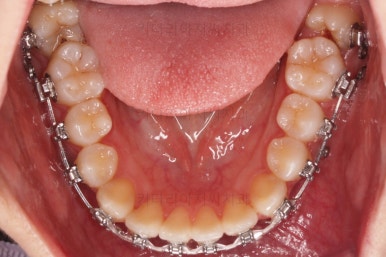

부산교정 키다리아저씨치과에 처음 내원하셨을 당시의 입안 모습과 X-ray 사진입니다.

맨 안쪽 치아가 마치 사랑니인 것처럼 누워있고 애매하게 나와있었어요.

문제는 해당 치아가 썩었다는건데 기울어 있는 치아를 제대로 치료할 방법은 사실상 없죠. 앞에 치아에 가려진 부분이 썩었으니깐요.

초진 시의 다른 부위들 사진입니다.

약간의 주걱턱 느낌에 약간의 돌출감, 전반적인 치열의 가지런한 느낌은 나쁘진 않았지만 약간의 불량한 교합상태였어요.